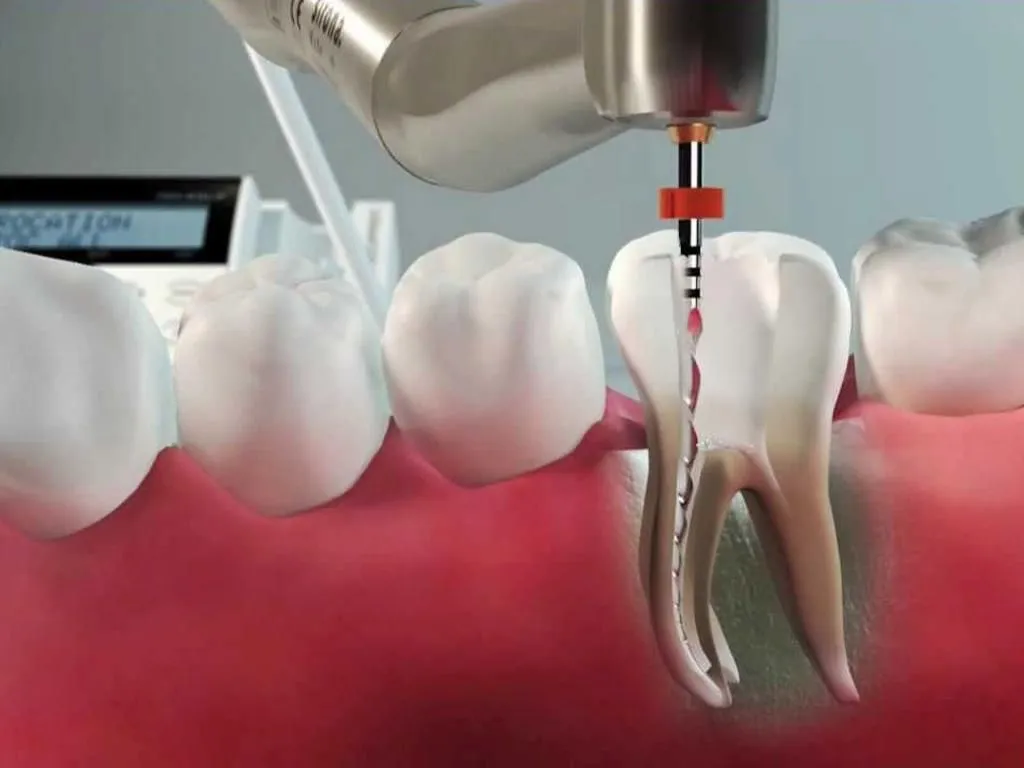

Limpeza e Modelagem Interna: Com o dente anestesiado, o profissional acessa a câmara pulpar. Ferramentas finíssimas, as limas endodônticas, entram em ação para remover todo o tecido inflamado ou infectado. Elas também ajudam a alargar e modelar os canais radiculares, preparando o terreno para a desinfecção.

Desinfecção Profunda: A higiene interna é crucial. Soluções irrigadoras, como o hipoclorito de sódio, são usadas para lavar e desinfetar os canais, eliminando bactérias e garantindo um ambiente limpo. Esse passo é um dos mais importantes para o sucesso do tratamento.

O Processo de Limpeza: O dentista utiliza instrumentos específicos para limpar e desinfetar os canais radiculares. A remoção do tecido doente e a desinfecção são etapas cruciais para eliminar a infecção e prevenir problemas futuros. É um trabalho minucioso de higienização interna.

Irrigação Inteligente: A irrigação contínua durante o preparo do canal garante que a solução desinfetante alcance todas as áreas. Técnicas modernas e instrumentos ultrassônicos potencializam a ação desses líquidos, garantindo uma limpeza profunda e completa.